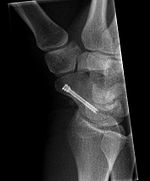

Scaphoid fracture before and after operation

Fractures of the scaphoid are the most common of the carpal bone injuries, because of its connections with the two rows of carpal bones.[1]:177

The scaphoid can be slow to heal because of the limited circulation to the bone. Fractures of the scaphoid must be recognized and treated quickly, as prompt treatment by immobilization or surgical fixation increases the likelihood of the bone healing in anatomic alignment, thus avoiding mal-union or non-union.[5] Delays may compromise healing. Failure of the fracture to heal ("non-union") will lead to post-traumatic osteoarthritis of the carpus.[1]:189 One reason for this is because of the "tenuous" blood supply to the proximal segment.[2] Even rapidly immobilized fractures may require surgical treatment, including use of a headless compression screw such as the Herbert screw to bind the two halves together.

Healing of the fracture with a non-anatomic deformity (frequently, a volar flexed "humpback") can also lead to post-traumatic arthritis. Non-unions can result in loss of blood supply to the proximal pole, which can result in avascular necrosis of the proximal segment.

Scaphoid fractures may be difficult to diagnose via plain x-ray, so repeat x-ray may be used at a later date, or cross-sectional imaging via MRI or CT scan.[5]